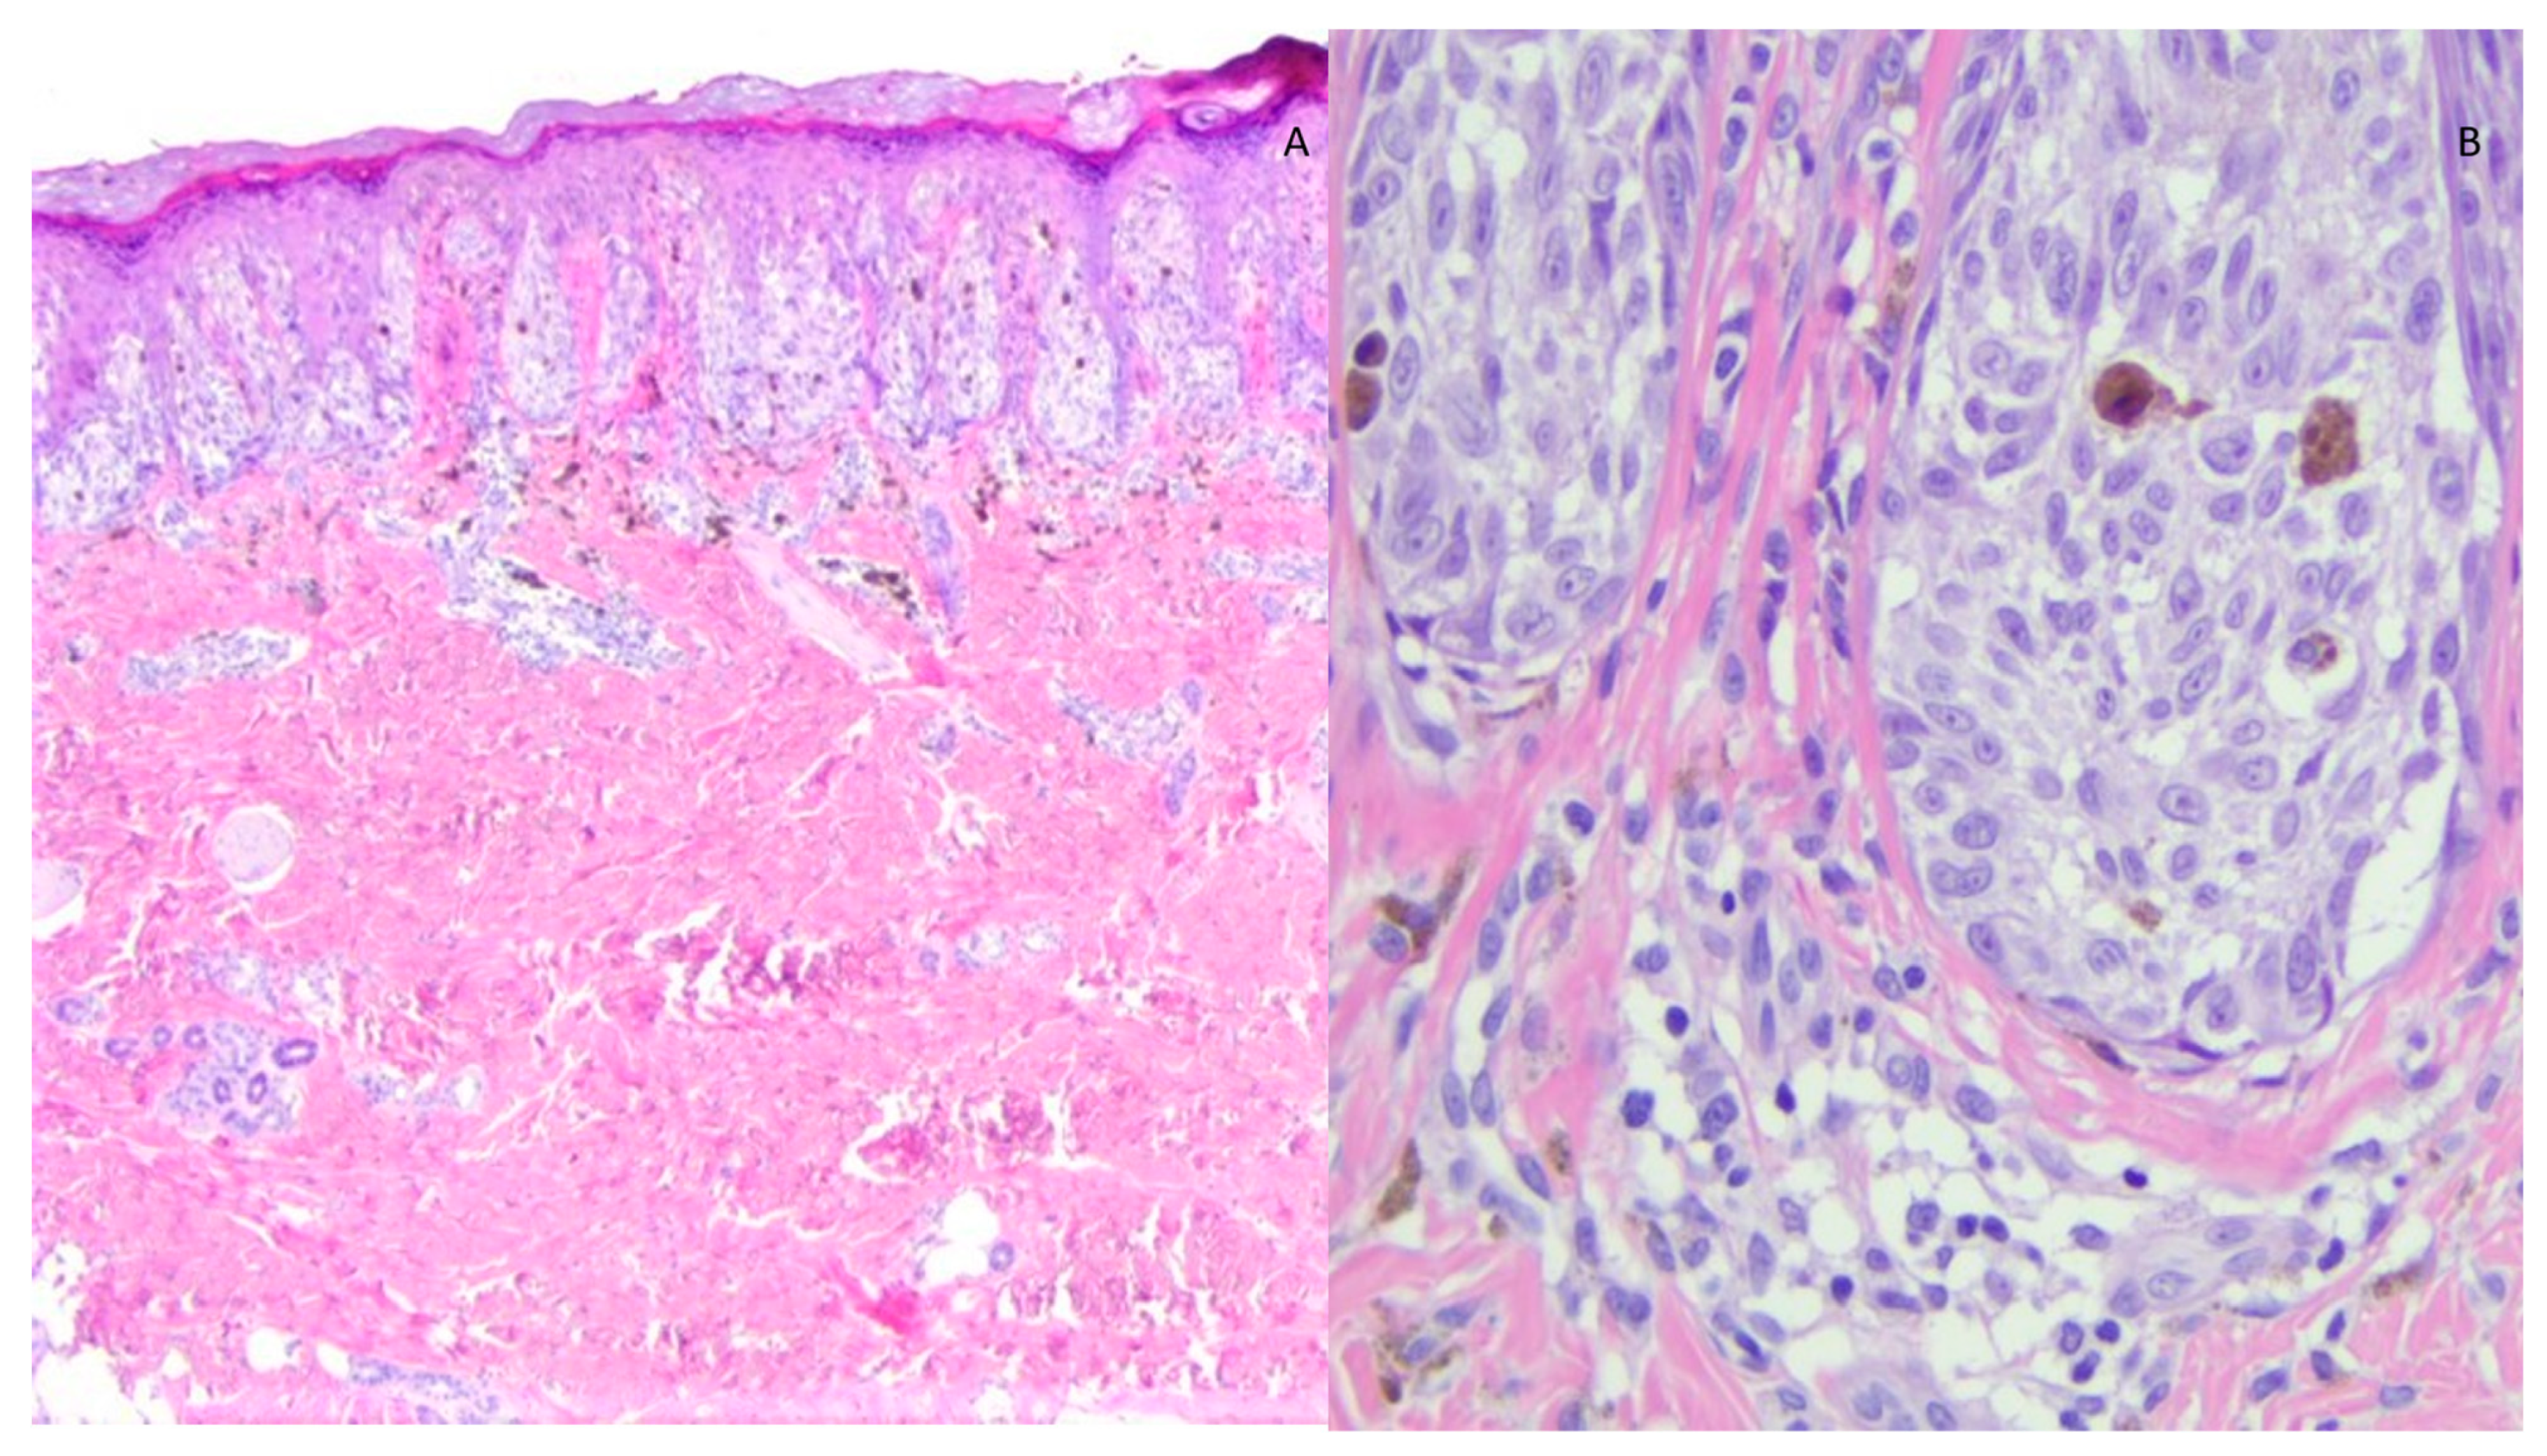

3. Results

4. Discussion